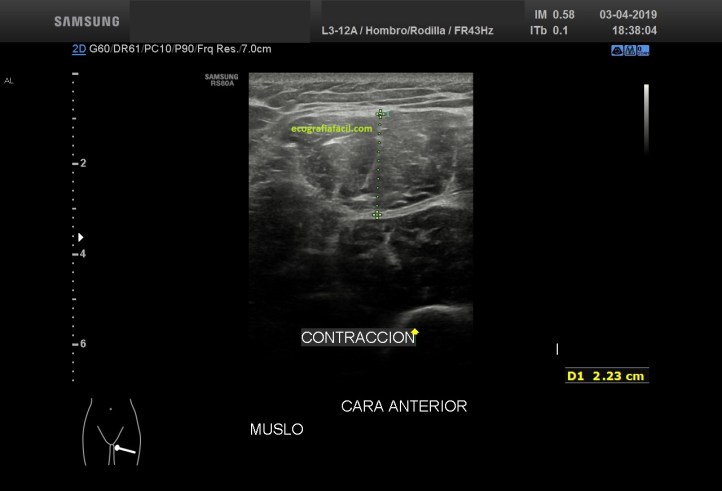

Comprobando los cambios objetivados en la ecoarquitectura del músculo figuras 4 y 5, le pido al paciente que realice contracción del muslo normal y del patológico, observando claros cambios de la ecoarquitectura y de comportamiento en la exploración dinámica.Mira:

El Recto anterior afectado no se contrae correctamente (fig 6), de facto, casi no sufre variación respecto de su situación basal, el normal sufre una hipoecogenicidad aumentada, semiológicamente normal en la contracción (fig 7) y un cambio en su aspecto respecto de la situación de reposo muscular.